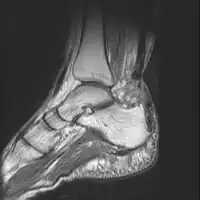

MRI can be used to discern incomplete ruptures from degeneration of the Achilles tendon, and MRI can also distinguish between paratenonitis, tendinosis, and bursitis. This technique uses a strong uniform magnetic field to align millions of protons running through the body. These protons are then bombarded with radio waves that knock some of them out of alignment. When these protons return they emit their own unique radio waves that can be analysed by a computer in 3D to create sharp cross sectional image of the area of interest. MRI can provide unparalleled contrast in soft tissue for an extremely high quality photograph making it easy for technicians to spot tears and other injuries.

Achilles tendon rupture